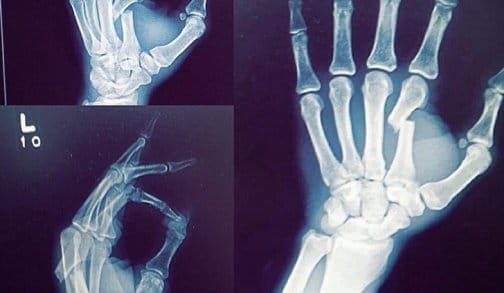

Бывший чемпион Bellator в полулегком весе, Дэниел Штраус, в минувшее воскресенье чуть было не распрощался с жизнью, попав в серьезную аварию на мотоцикле.

В настоящий момент боец находится в сознании и двигает всеми конечностями, но полная информация о его травмах и состоянии отсутствует.